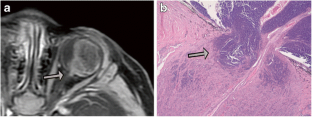

Fig. 3